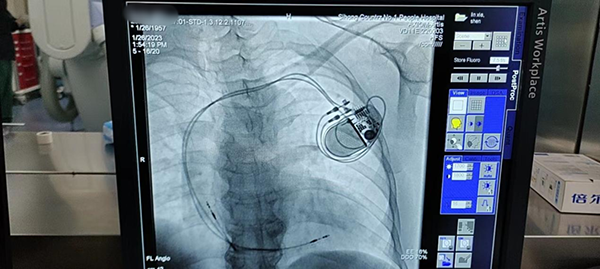

近期癥狀又有所加重,于是她來到徐州醫(yī)科大學(xué)附屬醫(yī)院泗洪分院就診,心內(nèi)科接診后,診斷為病態(tài)竇房結(jié)綜合征,行動態(tài)心電圖提示:平均心率42次/MIN,最大RR間歇3.6s,此時患者已有具備“心臟永久起搏器”植入指征,如果不及時救治,心臟隨時可能停跳,危及生命。

由于患者病情緊急,1月26日(大年初五),李承宗主任放棄春節(jié)假期趕到泗洪,在他指導(dǎo)下,醫(yī)護(hù)團(tuán)隊默契配合、細(xì)致操作,僅用時90分鐘,就成功實施心臟永久起搏器植入手術(shù)。沈阿姨術(shù)后高興地說:“我這胸悶的感覺沒有了,心臟跳得也有勁了”。她兒子表示十分感謝:“再也不用奔走異地求醫(yī),在家門口就有一流的專家,可以享受到一流的醫(yī)療技術(shù),我們年后也可以放心地出去打工了”。

這是泗洪縣第一人民醫(yī)院的首臺永久起搏器植入術(shù),填補(bǔ)了醫(yī)院的技術(shù)空白。去年在李承宗主任的幫扶下,科室先后開展了室上性心動過速、心房顫動的射頻消融術(shù),真正實現(xiàn)技術(shù)下沉,補(bǔ)齊縣醫(yī)院醫(yī)療服務(wù)短板,標(biāo)志著縣級醫(yī)院在心臟起搏與電生理專業(yè)的全覆蓋。